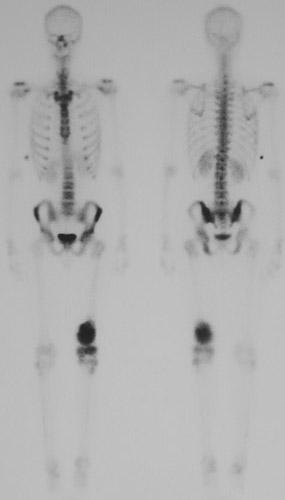

This bone scan demonstrates a "hot spot" of increased uptake in the distal left femur.